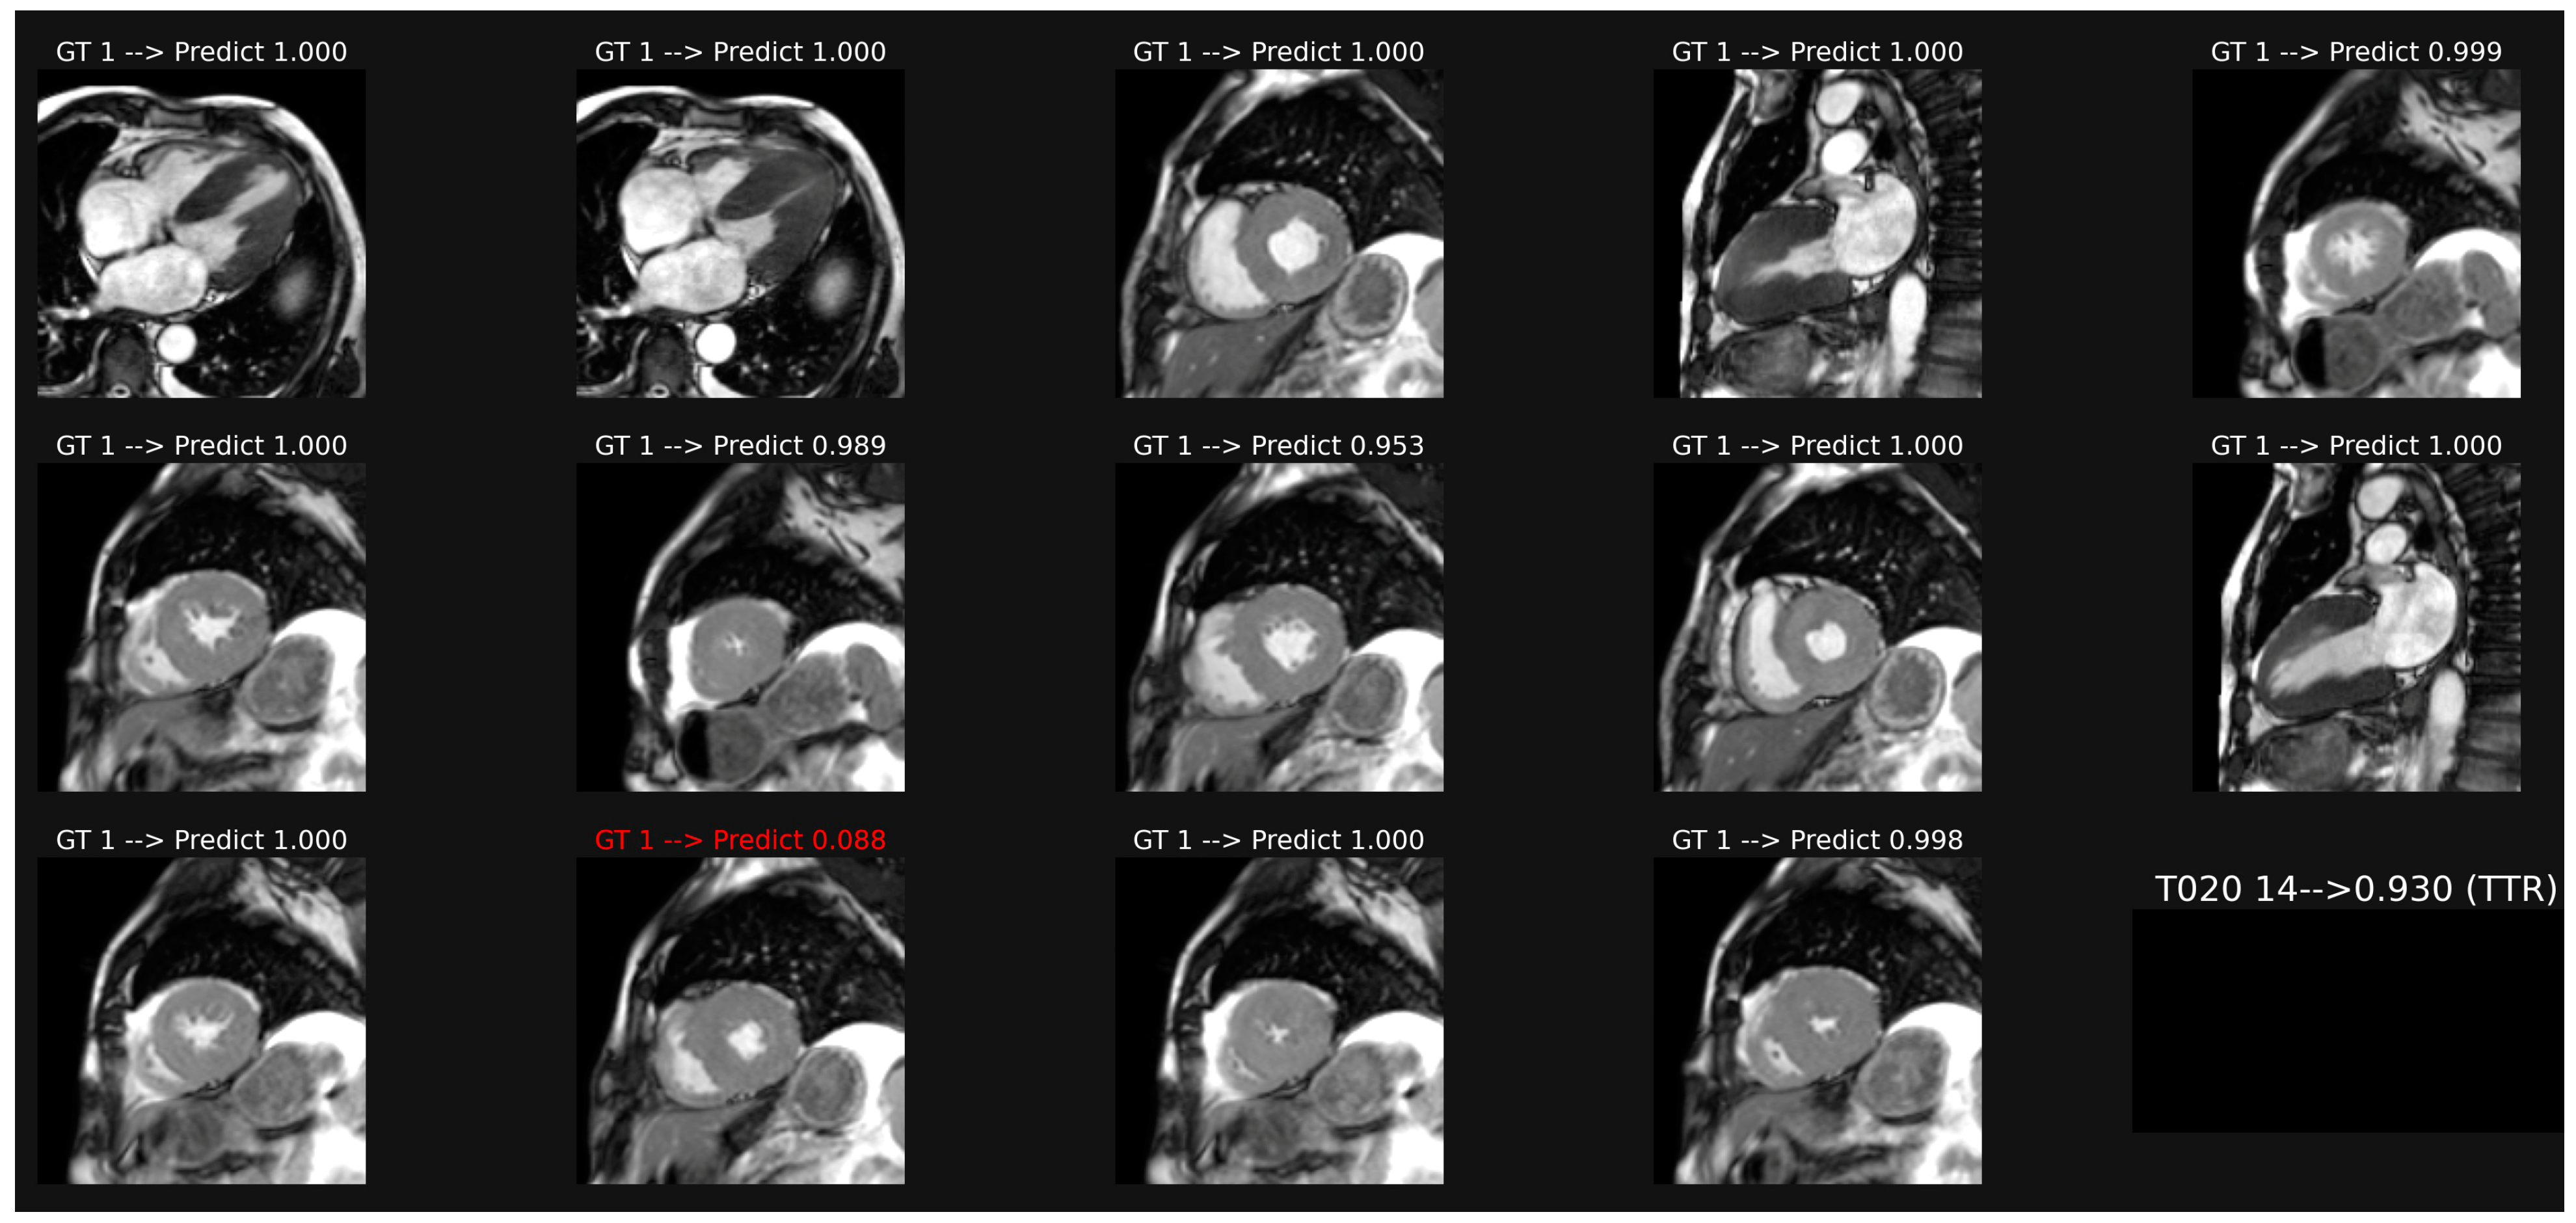

3.1. Classification of Cine-MR Images

3.2. Classification of LGE Images